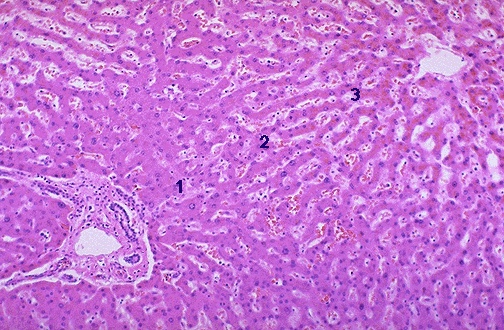

This is normal liver at medium power with zone 1 in periportal region, zone 2 in the middle of the lobule, and zone 3 in centrilobular region. A central vein and a portal triad define the lobule.